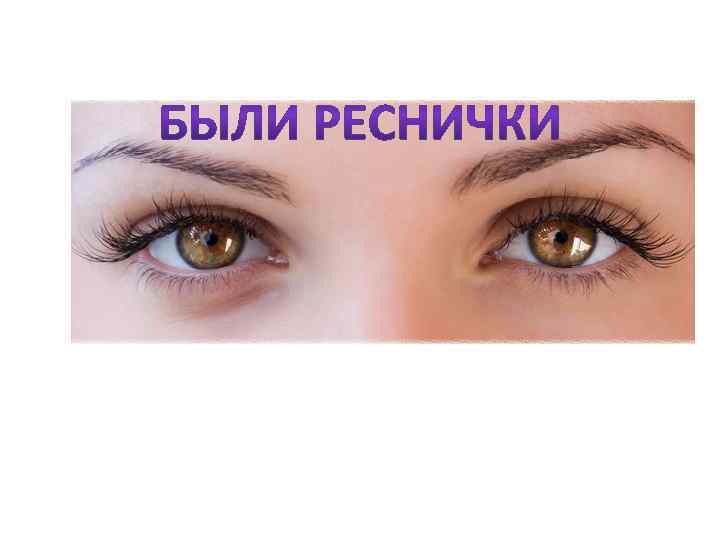

Факторы риска Недостаточное увлажнение дыхательной смеси Высушивание трахеи и бронхов

Факторы риска Недостаточное увлажнение дыхательной смеси Высушивание трахеи и бронхов

Факторы риска Недостаточное увлажнение дыхательной смеси ! Слизистая оболочка трахеи и бронхов обязательно должна быть укрыта секретом

Факторы риска Недостаточное увлажнение дыхательной смеси ! Слизистая оболочка трахеи и бронхов обязательно должна быть укрыта секретом

Факторы риска Недостаточное увлажнение дыхательной смеси • естественное удаление бактерий • состояние эпителия трахеи и бронхов

Факторы риска Недостаточное увлажнение дыхательной смеси • естественное удаление бактерий • состояние эпителия трахеи и бронхов

Движение клеток реснитчатого эпителия Движение вперед 1 – 3 Обратное движение 4 – 8

Движение клеток реснитчатого эпителия Движение вперед 1 – 3 Обратное движение 4 – 8

Оптимальное увлажнение Достаточная продукция слизи Хороший транспорт Экономит энергию и воду Защитная функция

Оптимальное увлажнение Достаточная продукция слизи Хороший транспорт Экономит энергию и воду Защитная функция